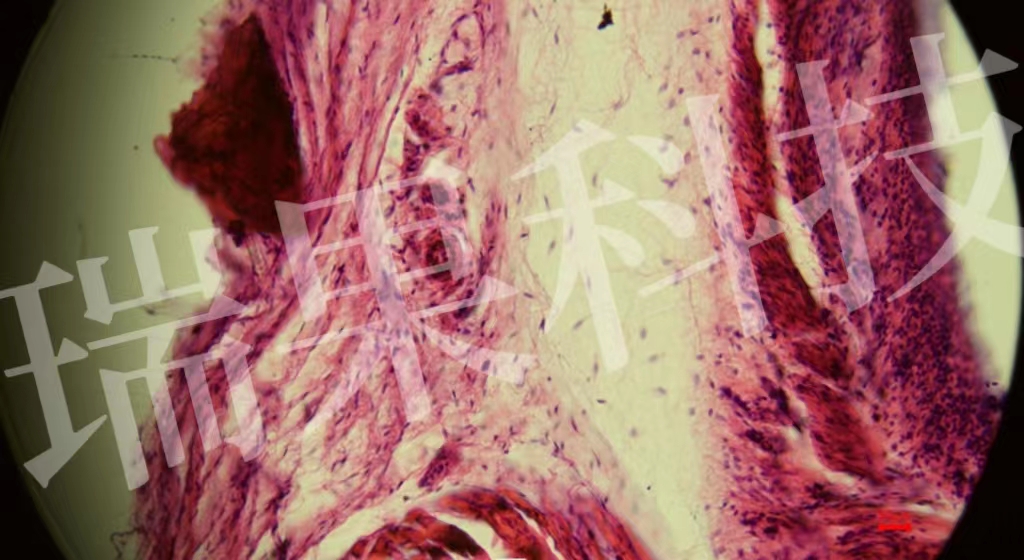

HE染色:蘇木精 - 伊紅染色法 ( hematoxylin-eosin staining ) ,簡稱HE染色法 ,石蠟切片技術(shù)里常用的染色法之一 。蘇木精染液為堿性 ,主要使細胞核內(nèi)的染色質(zhì)與胞質(zhì)內(nèi)的核酸著紫藍色 ;伊紅為酸性染料 ,主要使細

HE染色:蘇木精 - 伊紅染色法 ( hematoxylin-eosin staining ) ,簡稱HE染色法 ,石蠟切片技術(shù)里常用的染色法之一 。蘇木精染液為堿性 ,主要使細胞核內(nèi)的染色質(zhì)與胞質(zhì)內(nèi)的核酸著紫藍色 ;伊紅為酸性染料 ,主要使細胞質(zhì)和細胞外基質(zhì)中的成分著紅色 。HE染色法是組織學(xué)、胚胎學(xué)、病理學(xué)教學(xué)與科研中最基本、使用最廣泛的技術(shù)方法。